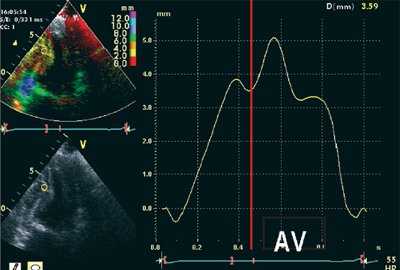

Методика импульсно-волновой ТД

Анализ продольного движения миокарда проводился в верхушечном 4-камерном срезе сердца с синхронной записью мониторного отведения ЭКГ при задержке дыхания пациента в течение 5-10 сердечных циклов (рис. 1). Контрольный объем (5x8 мм) ТД размещался в латеральной и медиальной частях фиброзного кольца митрального клапана (МФК). Точкой начала отсчета временных фаз считали зубец R ЭКГ. Проводился анализ параметров ТД от латеральной (МФКл) и медиальной (МФКм) частей фиброзного кольца митрального клапана: ТМРИ вычислялся по ТД в медиальной и латеральной частях МФК по графикам максимальной скорости движения МФК как отношение разницы временного интервала между началом положительной волны ИВС до начала «Еm» (a’) и временем систолической волны Sm (b’), по формуле:

![Принцип расчета ТМРИ по ТД фиброзного кольца митрального клапана]()

Рис. 1. Принцип расчета ТМРИ по ТД фиброзного кольца митрального клапана.